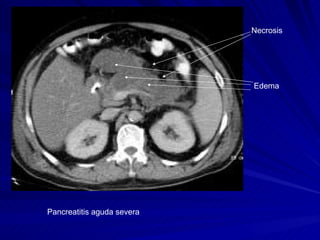

TOMOGRAFIA COMPUTADA HALLAZGOS PANCREATITIS AGUDA: Crecimiento de la glándula Pérdida de nitidez o claridad de sus bordes Hipodensidad de su parénquima

TOMOGRAFIA COMPUTADA La TAC. es el estudio de oro para el diagnóstico de: Pancreatitis aguda y gran apoyo para el diagnóstico de Pancreatitis crónica.

Pancreatitis aguda severa Necrosis  Edema

TOMOGRAFIA COMPUTADA HALLAZGOSPANCREATITIS AGUDA: Crecimiento de la glándula Pérdida de nitidez o claridad de sus bordes Hipodensidad de su parénquima

TOMOGRAFIA COMPUTADA LaTAC. es el estudio de oro para el diagnóstico de: Pancreatitis aguda y gran apoyo para el diagnóstico de Pancreatitis crónica.